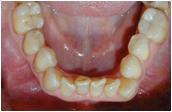

Eine 64jährige Patientin litt unter Engständen im Frontbereich. Der linke Eckzahn im Unterkiefer stand außen im Kreuzbiss, den die Patientin als „Vampirzahn“ bezeichnete. Für die Ausformung des Zahnbogens müsste ein Frontzahn im Unterkiefer entfernt werden. Die Behandlung wurde mit Hilfe der Invisalign Technik durchgeführt. Die Behandlung hat zehn Monate gedauert.

Engstand im Unterkiefer Front

Kreuzbiss des Eckzahnes im Unterkiefer links